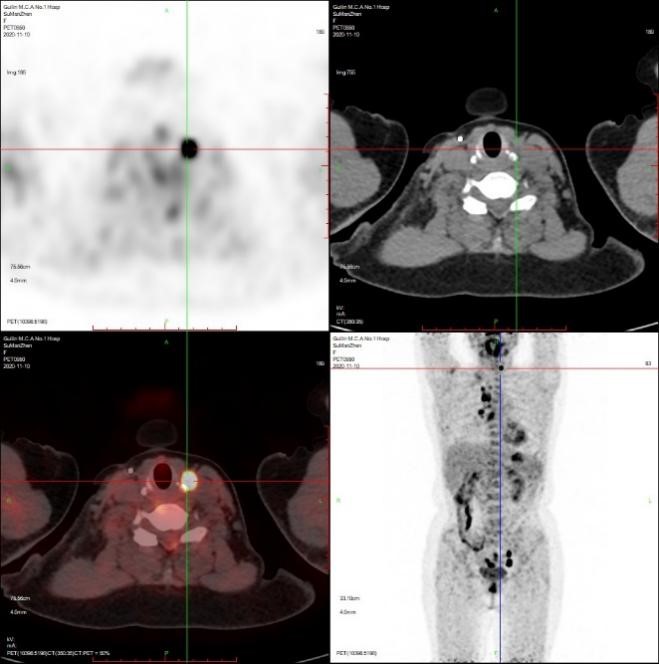

患者粟女士,57岁,既往甲状腺乳头状癌病史6年,近1月来反复咳嗽,当地CT提示肺部占位,为进一步明确诊断,至附属医院核医学科行PET/CT全身检查,提示颈部淋巴结、双肺及子宫内膜多发异常高代谢病灶。

核医学科治疗与影像组医师团队一起认真判读患者PET/CT图像,针对异常摄取病灶,反复评估穿刺进针路径及评估其安全性,技术组全力配合,通过PET/CT精准定位,成功为患者取得了肺及淋巴结组织标本,整个操作过程顺利,手术耗时仅半小时,术中及术后患者无明显不适,术后复查未见血气胸及副损伤。

之后根据PET/CT子宫内膜摄取病灶定位,协助妇科获取了相应部位子宫内膜病理组织。术后完成病理定性、肿瘤组织学亚型分类、分子病理检测。病理提示颈部淋巴结为甲状腺乳头状癌颈部淋巴转移;肺占位为腺泡型肺腺癌(免疫组化支持肺原发来源)。子宫内膜病理提示子宫内膜癌。

患者全身PET/CT图像